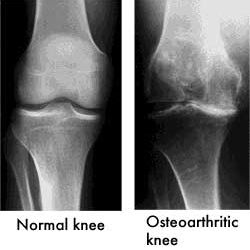

Hyaluronic acid or Synvisc-One is a treatment for osteoarthritis. It is a clear gel that is delivered by a small injection into the joint. It is made from a natural substance that lubricates the joint and may provide up to 6 months of osteoarthritis knee pain relief with one injection. Although doctors and researchers are yet to find a cure for osteoarthritis, they have discovered a number of treatments and pain management programs to lessen the pain, improve mobility and make your life easier.